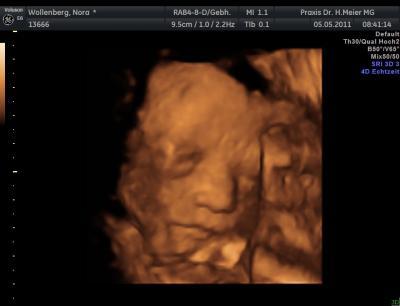

Meine Prinzessin 3D :)

NoraElisa